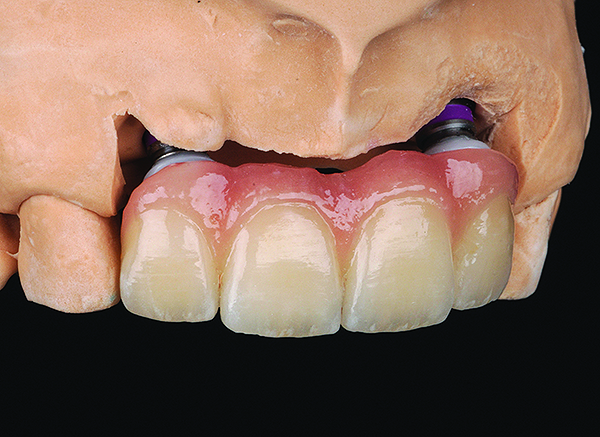

Figure 13 Image of a porcelain-layered zirconia framework (CL-IIIb) with layered pink porcelain for the gingiva (image courtesy of Aram Torosian, MDC).

Figure 13